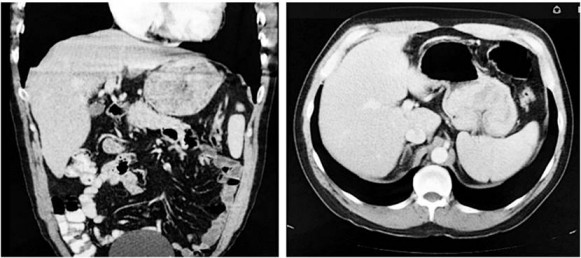

La tomografía contrastada de tórax y abdomen evidencia una masa gástrica y se descartan lesiones metastásicas (Figura 1). Se realiza entonces la resección quirúrgica mediante una gastrectomía total con disección ganglionar D1 y la reconstrucción en Y de Roux. La evolución posoperatoria es favorable y es dado de alta a los 7 días.